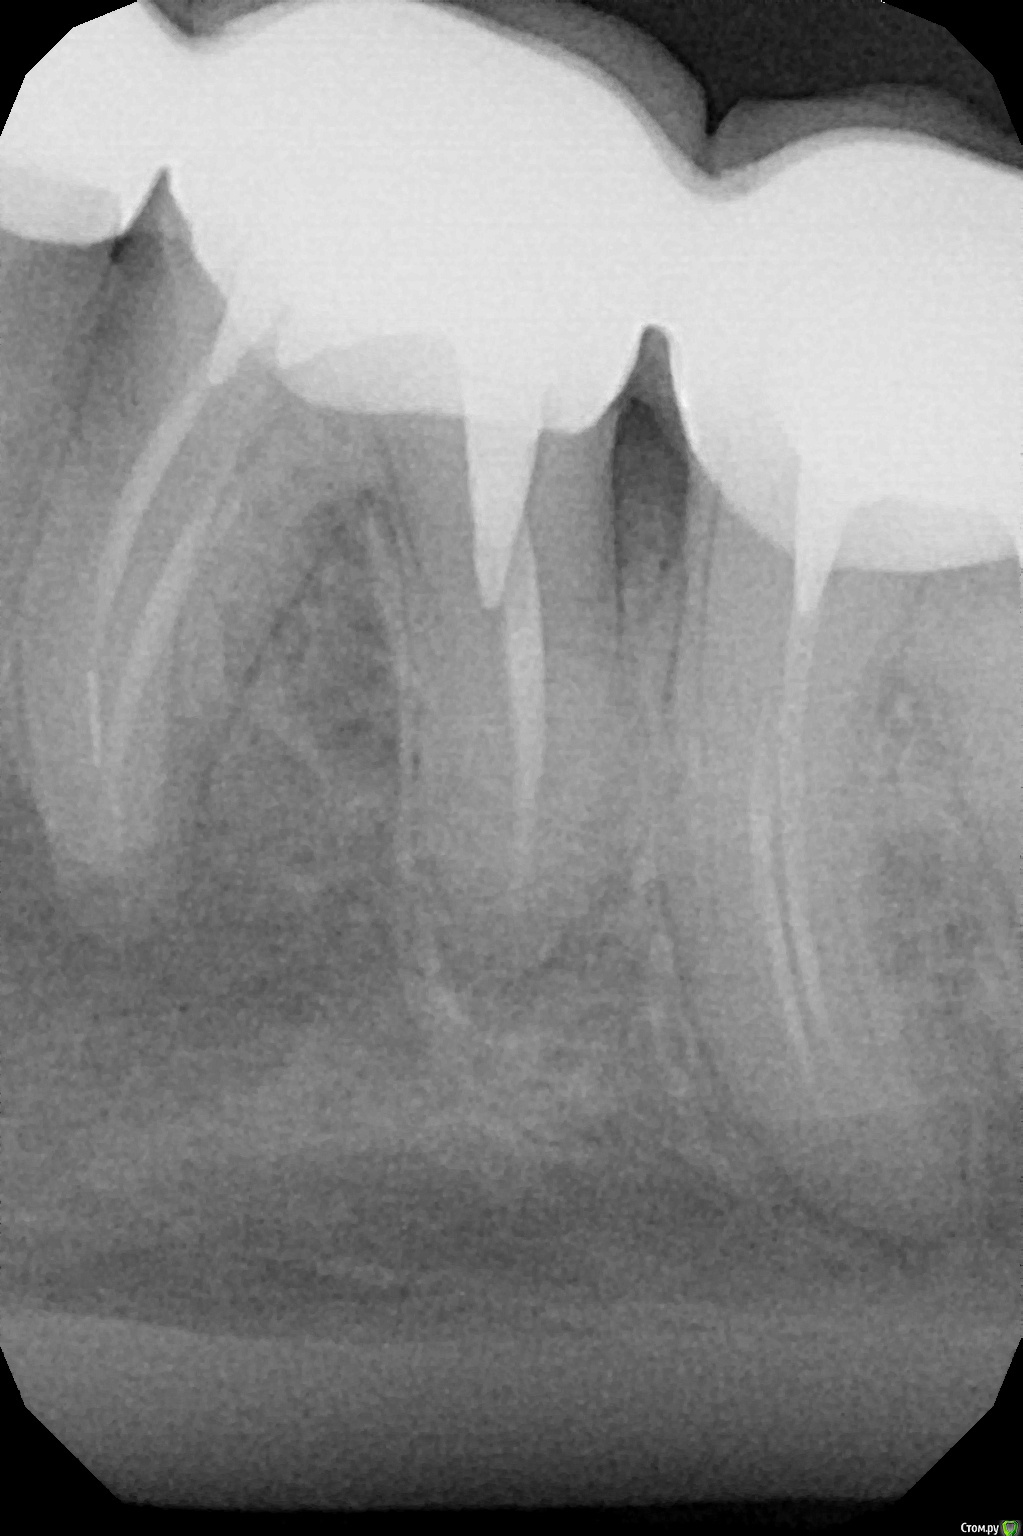

сирена Опубликовано 4 сентября, 2018 Поделиться Опубликовано 4 сентября, 2018 Снимайте коронки и удаляйте шестой зуб.Перелечить его вряд ли получится.Попробовать можно,конечно,но это будет дорого.И без гарантии. Ссылка на комментарий

red_butler Опубликовано 5 сентября, 2018 Поделиться Опубликовано 5 сентября, 2018 Снимайте коронки и удаляйте шестой зуб.Перелечить его вряд ли получится.Попробовать можно,конечно,но это будет дорого.И без гарантии.Очно нужно смотреть Боль, если по баллам, то 10 из 10 это больше на пульпит похоже 8 зуб запломбированный, но с нервами Ссылка на комментарий

saintdim Опубликовано 6 сентября, 2018 Автор Поделиться Опубликовано 6 сентября, 2018 Очно нужно смотреть это больше на пульпит похоже сходил в поликлинику с острой болью. Снял мост, врач сказала, что 6 зуб можно попробовать сохранить. Разрезала десну, убрала гной. Пью антибиотики и обезболивающее. Немного опухла щека, но врач сказала такое возможно. Единственное что беспокоит как будто ещё заморозка не прошла на щеке и нижней губе онимение. Боль гараздо меньше, но отдает в висок и голову со стороны зуба.полощу содой. Ссылка на комментарий